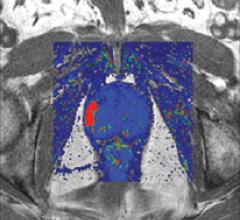

iCAD develops, engineers, manufactures and markets industry-leading Computer-Aided Detection (CAD) solutions that enable healthcare professionals to identify cancer and other life-threatening conditions earlier by making medical services more effective, more accessible and more affordable for patients worldwide. As the only independent, integrated CAD software and digitizer hardware company, we are able to reduce costs at each stage of the design, production and assembly process. We believe such vertical expertise results in better integration, lower production costs and reduced administrative overhead – factors which allow us to continuously enhance our Mammography, Computed Tomography and Digitizer solutions to pass savings onto our customers. iCAD’s position in the market has earned industry recognition with the receipt of Frost & Sullivan’s Growth Strategy Leadership award and MD Buyline’s continued recognition as “The Winning Combination” of Price and Performance.